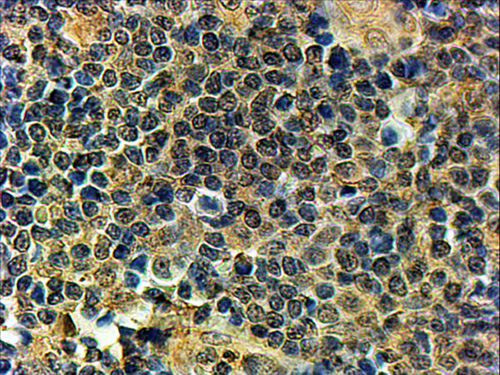

APG00388G (2 μg/ml) staining of paraffin embedded Human Tonsil. Steamed antigen retrieval with Tris/EDTA buffer pH 9, HRP-staining.